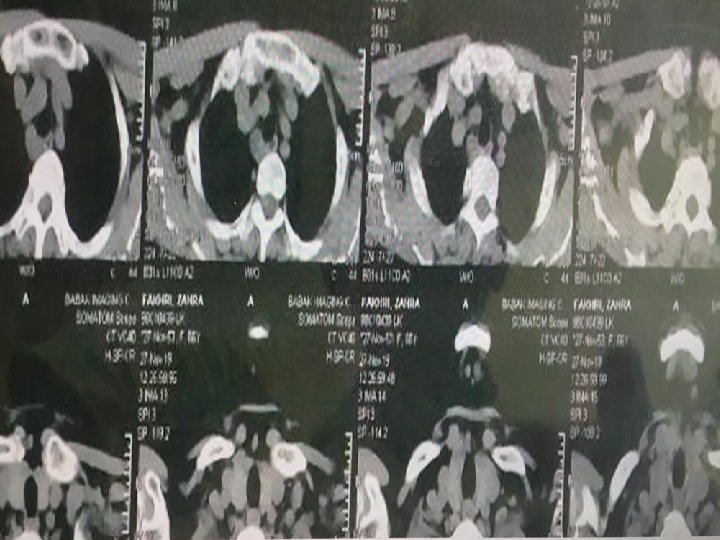

CT Scan axial of neck with and without IV Contrast 98/6/9

CT scan of chest with and without contrast 98/6/9